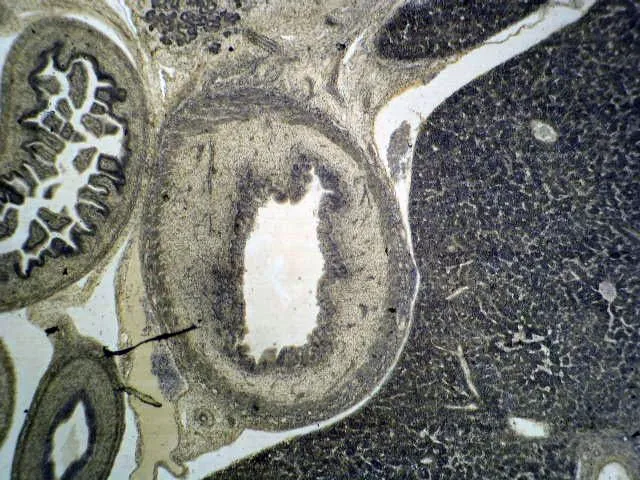

Sarkopenia, czy kreatyna może przywrócić funkcję mięśni?. Preparaty normalnego mięśnia. Widok USG, preparat pośmiertny oraz histologiczny.

Kreatyna w walce z osteosarkopenią

Wyobraź sobie, że twoje ciało to orkiestra. Kości są niczym solidne instrumenty – skrzypce, wiolonczele, kontrabasy – które nadają rytm i strukturę. Mięśnie to muzycy, którzy wprawiają te instrumenty w drgania i sprawiają, że powstaje melodia. Co się stanie, jeśli instrumenty zaczną pękać, a muzycy stracą siły? Tak właśnie objawia się osteosarkopenia: połączenie osłabienia kości